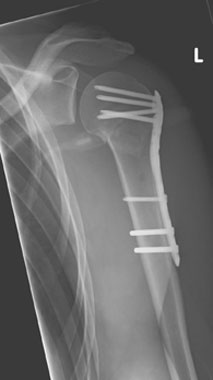

In diesem Fall ist eine winkelstabilen Plattenosteosynthese indiziert. Durch die winkelstabile Schraubenverankerung im Plattenlager und divergierenden Schraubenverlauf, welcher die ganze Breite des Kopffragmentes nutzt, wird eine hohe primäre Stabilität erreicht. Dies ermöglicht eine frühfunktionelle Übungsstabilität bei gleichzeitiger

Schmerzreduktion. |